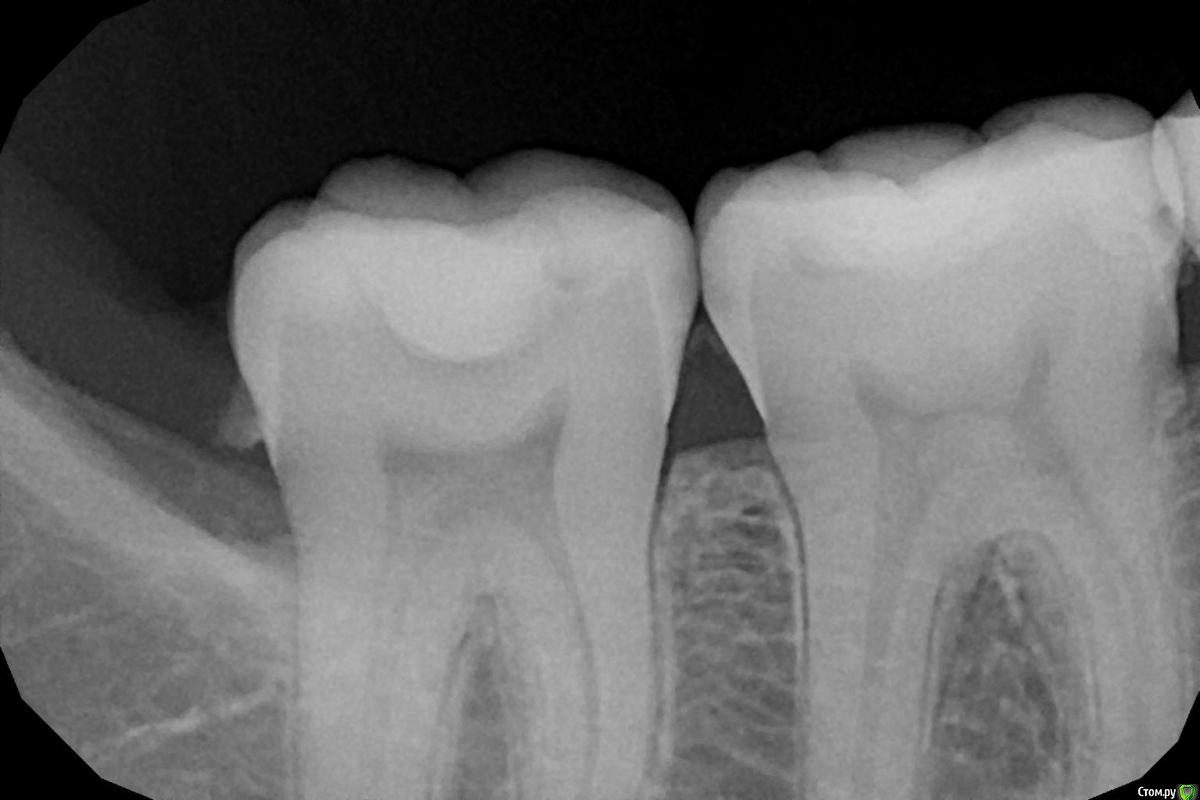

aleksandrovna_o Опубликовано 1 октября, 2020 Поделиться Опубликовано 1 октября, 2020 Здравствуйте, уважаемые врачи. Решила перестраховаться.Доктор, посмотрев на прицельные снимки, сказала, что есть кариес в двух местах. Один - его прямо срочно-срочно надо лечить, а другой - можно подождать максимум пол года. НО, у меня вообще там ничего не болит, нет реакции на горячее холодное, когда ем. Это как? такое разве бывает? посмотрите, пожалуйста, на снимки и скажите, действительно ли срочно нужно лечить.Первые два снимка - зубы 46-47. Там, если не ошибаюсь, кариес между зубами.Третий снимок — зубы 15,16,17.Буду очень признательна. Ссылка на комментарий

red_butler Опубликовано 1 октября, 2020 Поделиться Опубликовано 1 октября, 2020 Первые два снимка - зубы 46-47. Там, если не ошибаюсь, кариес между зубами. есть и кариес и камни такое разве бывает? еще как бывает 1 Ссылка на комментарий